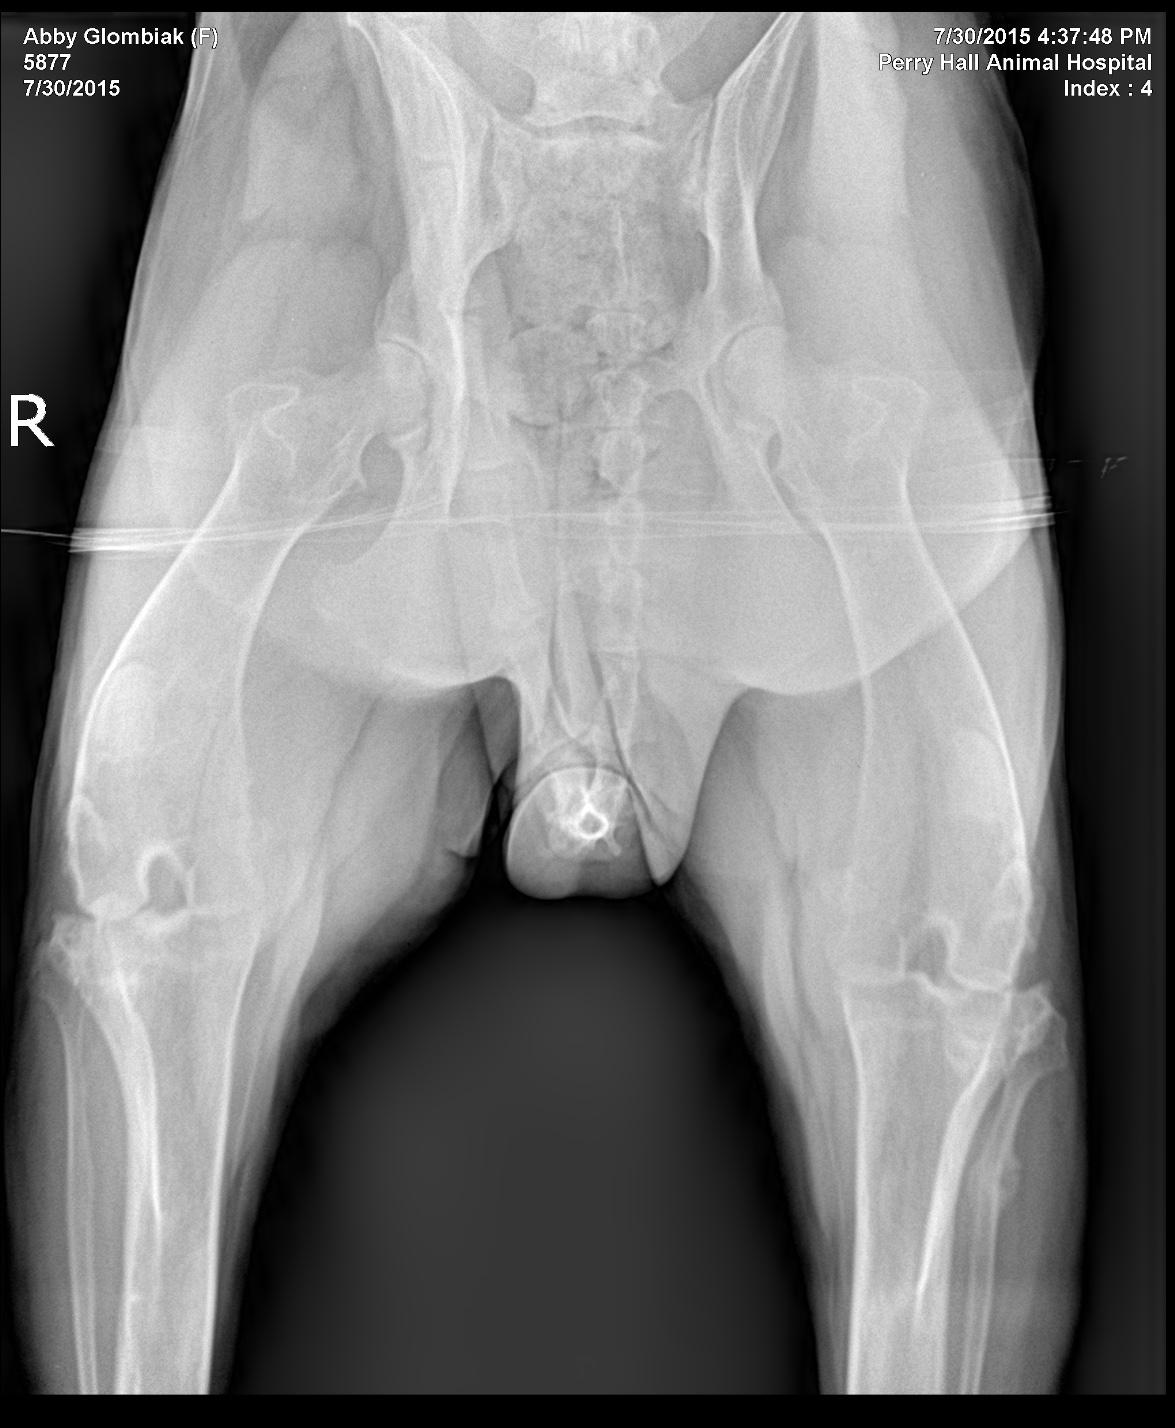

History of left hind leg lameness since February 2015. The patient had a hemilaminectomy on 5/28/5 which alleviated some of the lameness issues initially, but it progressed and the lameness has continued. Physical exam showed partial weight bearing consistently on the left hind leg with positive drawer and cranial tibial thrust. BCS 6.5/9. Neurological exam was WNL.

History of left hind leg lameness since February 2015. The patient had a hemilaminectomy on 5/28/5 which alleviated some of the lameness issues initially, but it progressed and the lameness has continued. Physical exam showed partial weight bearing consistently on the left hind leg with positive drawer and cranial tibial thrust. BCS 6.5/9. Neurological exam was WNL.